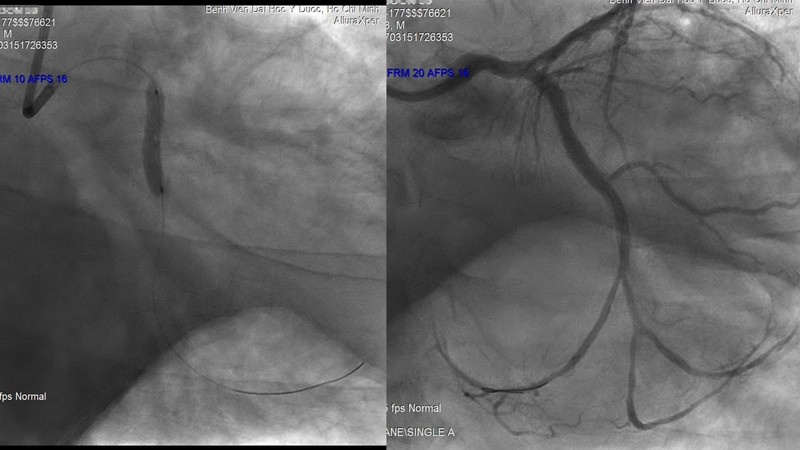

| Mạch máu của bệnh nhân trước và sau khi được các bác sĩ can thiệp. Ảnh: N.P. |

Ông Cang được chuyển đến khoa Cấp cứu Bệnh viện ĐH Y Dược TP.HCM. Bỏ qua các thủ tục nhập viện. người bệnh được chuyển lên phòng DSA để được can thiệp đặt stent (giá đỡ mạch máu), cấp cứu mạch vành qua da. 60 phút sau phẫu thuật, người bệnh đã thoát khỏi tình trạng nguy kịch.